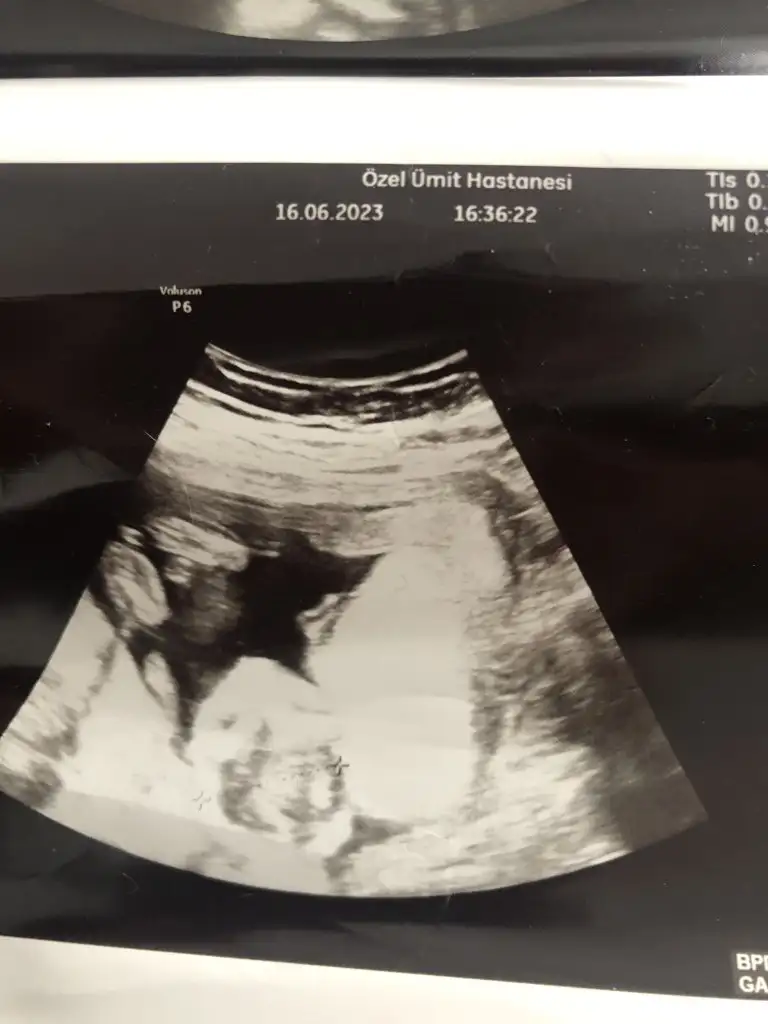

Bana da yorum yapar mısınız rica etsem 🙈 5+4 vajinal ultrason